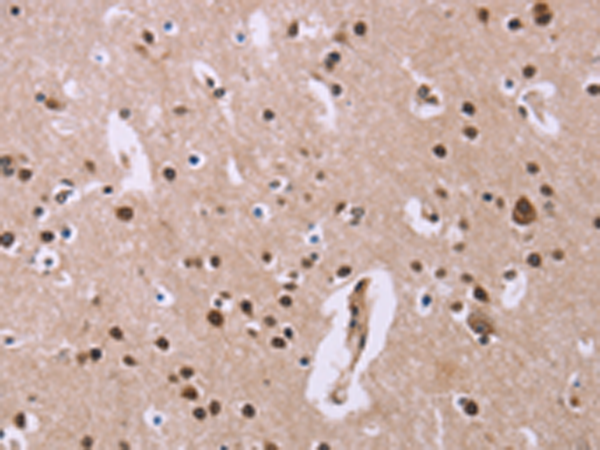

IHC positive control: |

Human brain |

IHC Recommend dilution: |

25-100 |